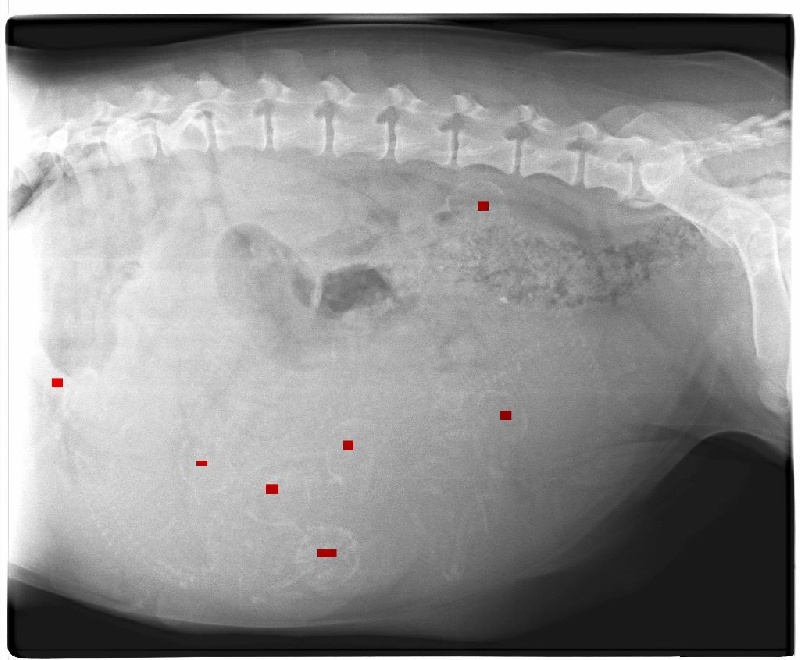

radio des bébés de Gertrude a 7 semaines